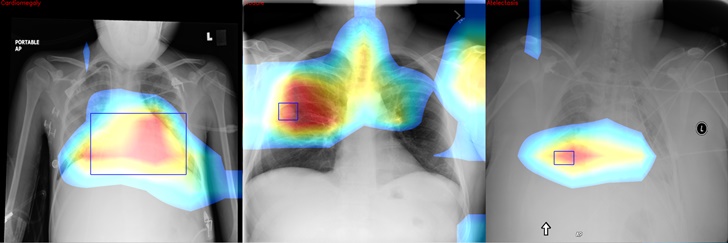

이후 그가 파이선 코딩으로 챗봇을 완성했습니다. 이 챗봇은 친구들이 그에게 왓츠앱으로 엑스레이 사진을 보내면 자동으로 엑스레이을 판독해 준다고 합니다.(Xray를 판독하는 인공지능은 기존에 공개된 ChexNet-Keras를 사용함)